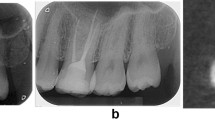

The restoration of all root segments was reapplied as described before, and the segments were incubated at 37 °C for 12 months in 100% humidity.33 The root segments were coated with silicone paste 2 mm apical to the cementoenamel junction to mimic a periodontal ligament.9 Subsequently, the teeth were embedded in resin blocks and positioned vertically. A cone-shaped rod with a diameter of 3.5 mm was used on a universal testing machine (Instron, Canton, MA, USA) directly over the root segments (Fig. 1). A load at a speed of 1 mm/min was driven downward vertically until a fracture occurred. The fracture pattern was recorded in Newtons.

FR values were tested with a universal testing machine (Instron, Canton, MA, USA) as it is an easy and commonly used method.9,22,41,42